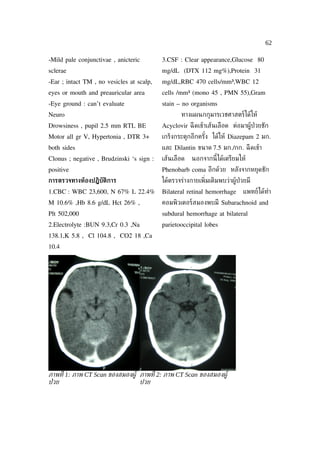

Interesting case/รายงานผู้ป่วยน่ าสนใจ......................................................................................................62